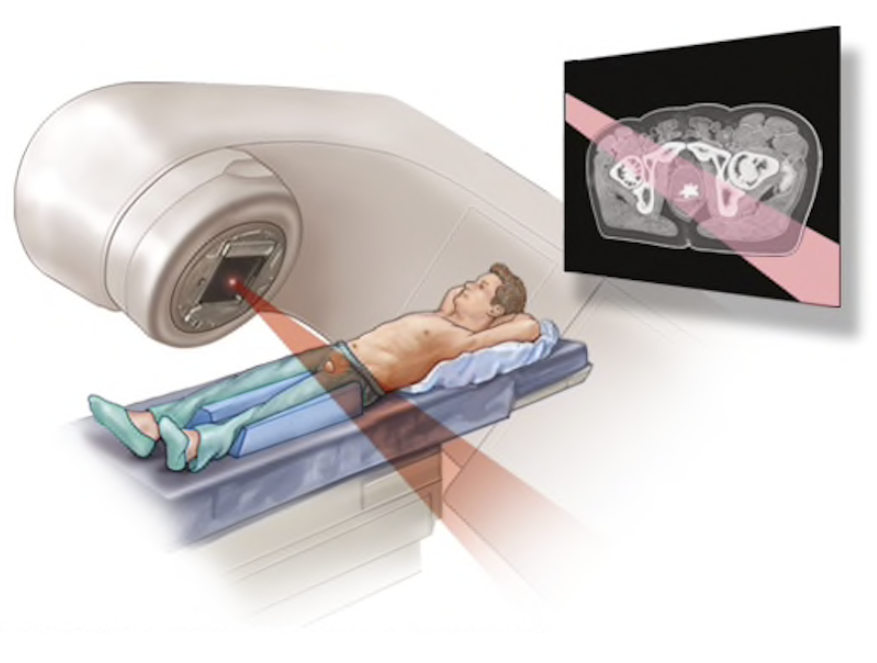

٢-ما حصل هو ان النظام اصبح يحسب كل اربعة كتل تدريع بواحدة، وبالتالي اعطى زيادة في الوقت اللازم لتعريض المرضى للإشعاع عن ما يجب أن يكون عليه (وكأن هناك تدريع كافي)، مما نتج عنه زيادة تعرض المرضى للإشعاع أكثر مما هو محدد لهم